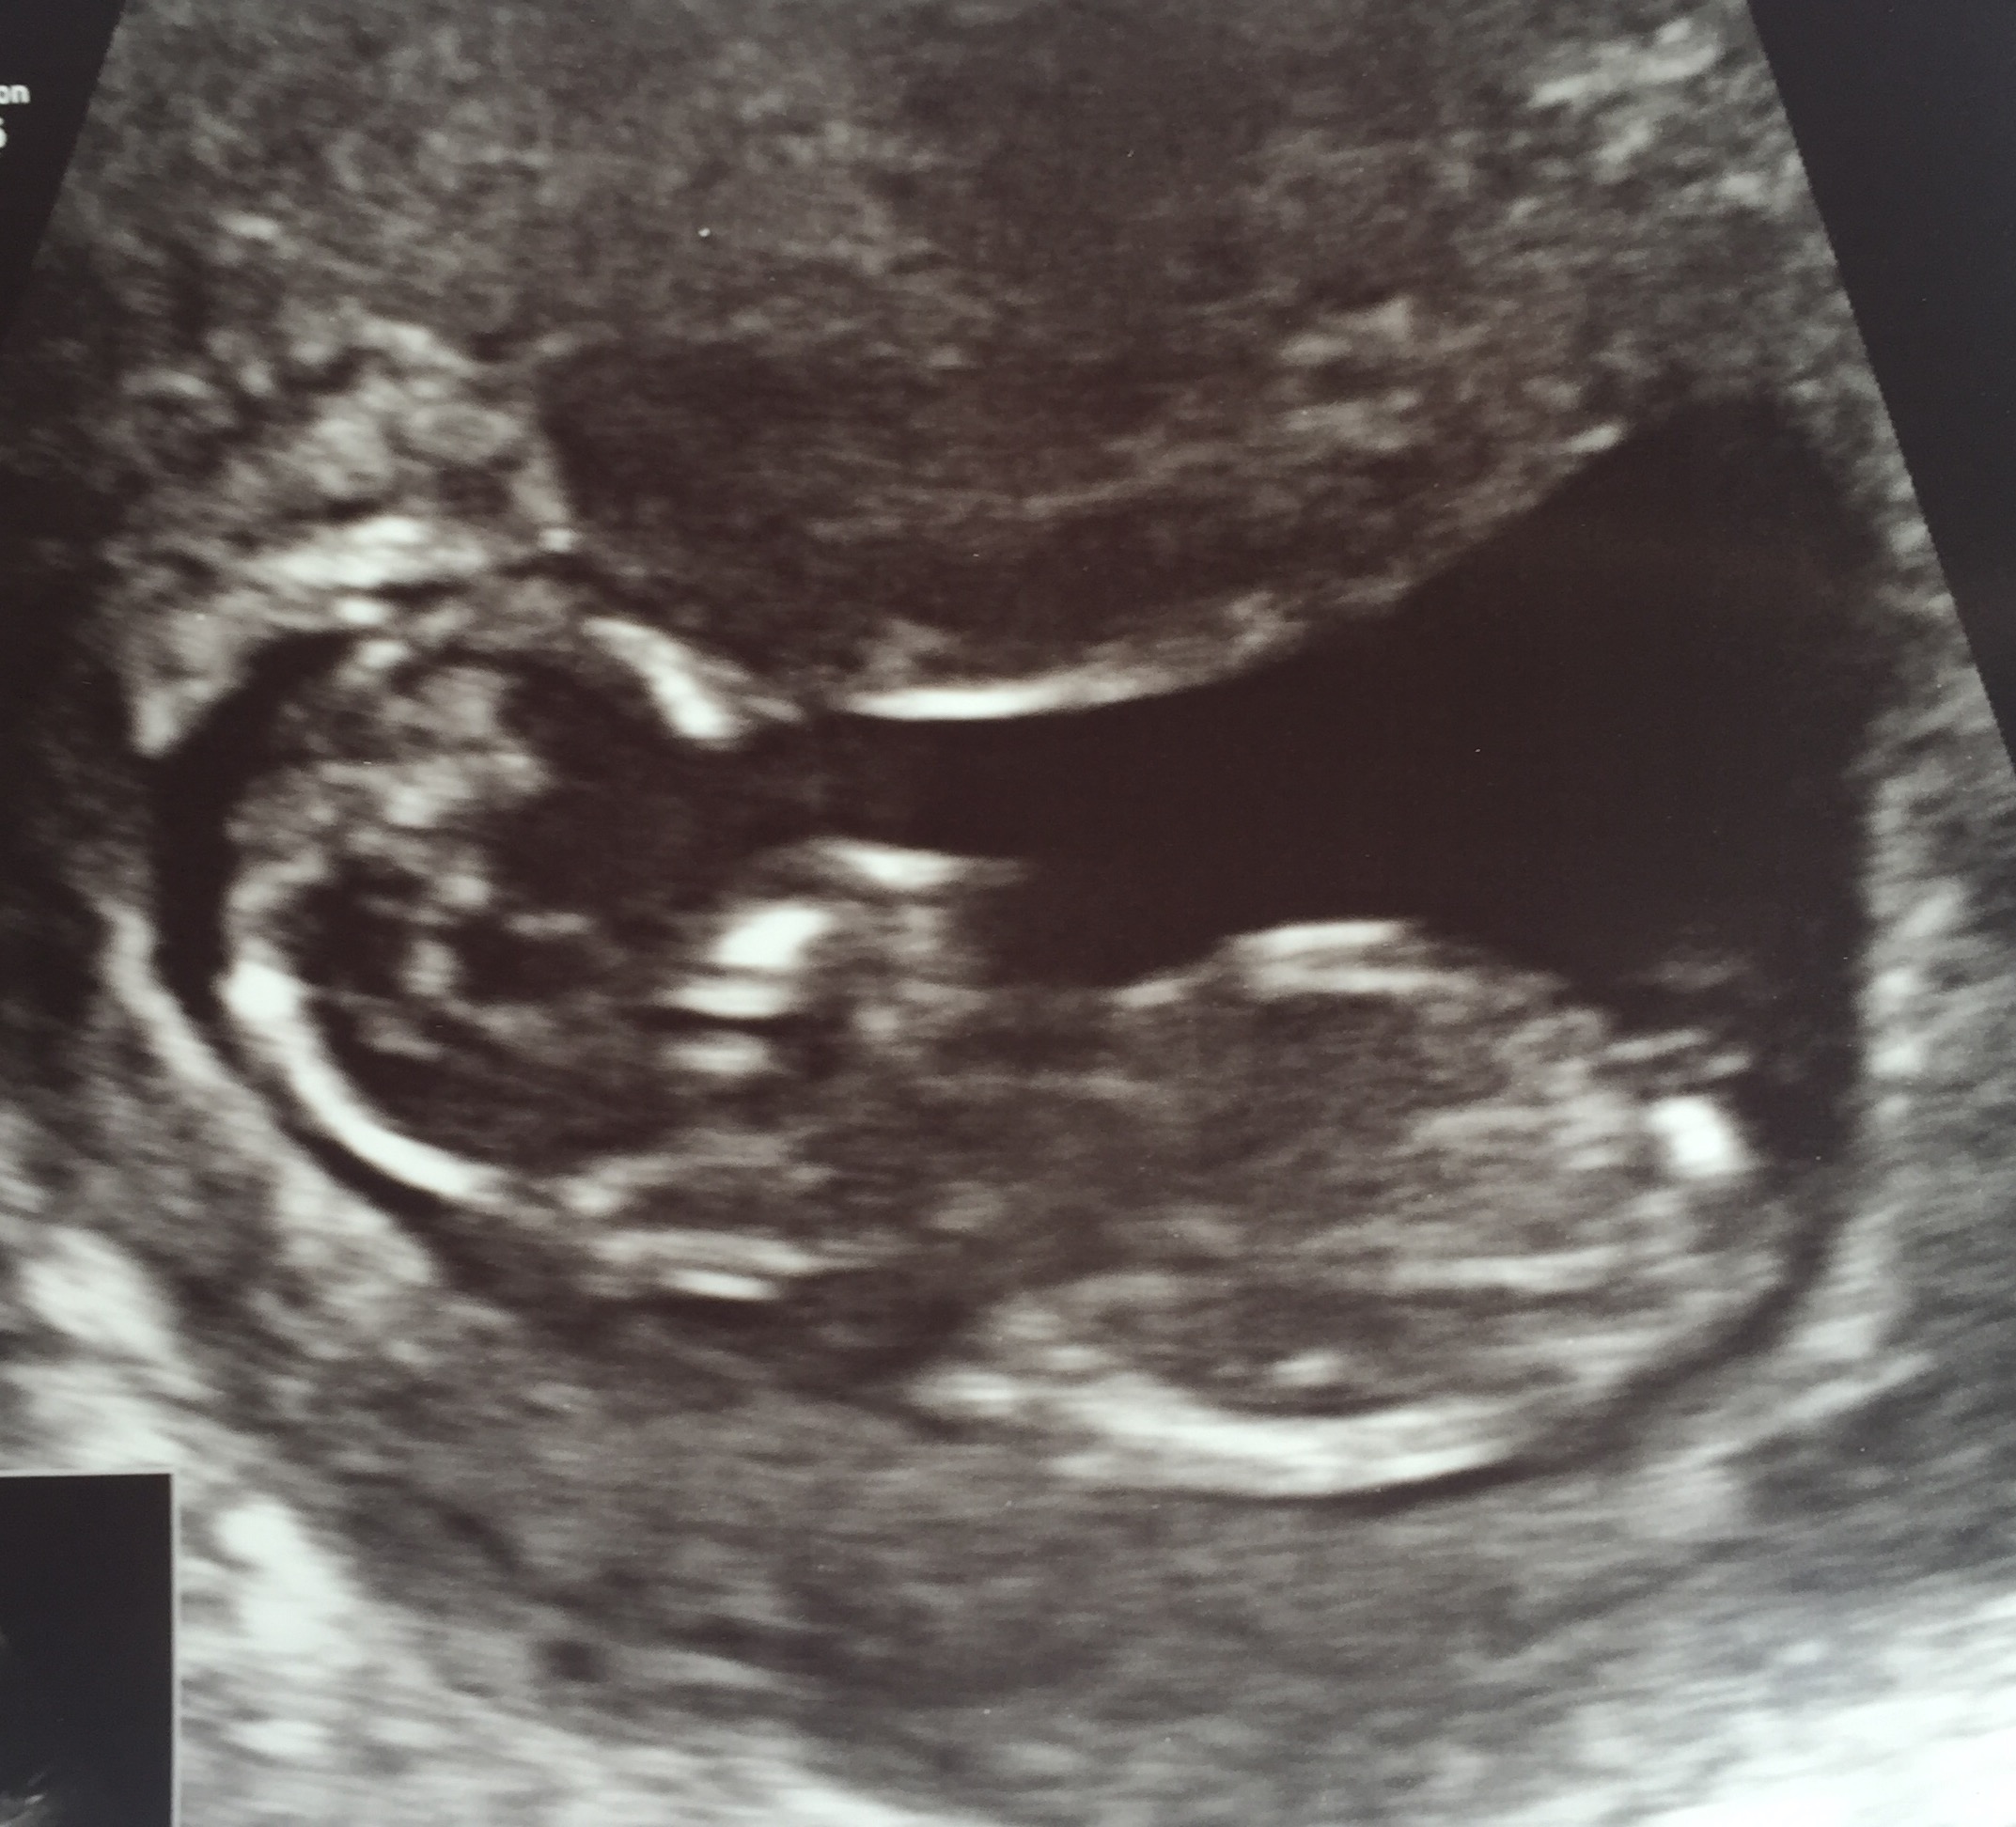

Would love to know what you think!!xxx

Yes it does but its a tricky one! Eeek im not confident guessing this one xx

Tentative girl guess

I'm also going to guess girl... Looks like nub is angled down. Hope you get clear pics on your next scan!

maybe girl

I'm leaning girl too on this one FX!!